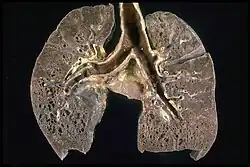

Da potenziell jedes Organ durch die Krankheit betroffen sein kann, richtet sich die Diagnostik nach der jeweiligen Beschwerdesymptomatik. Aufgrund der oft symptomlos verlaufenden Lymphknotenschwellungen wird die Sarkoidose nicht selten zufällig beim Röntgen-Thorax festgestellt. Je nach Befallsmuster und Zeichnung im Röntgenbild oder in der Computertomographie kann die pulmonale Sarkoidose in folgende Stadien (nach Scadding, 1961[15]) eingeteilt werden, wobei diese Einteilung oft die Schwere und die Prognose der Erkrankung nicht wiedergibt:[16]

- Stadium 0: Normalbefund der Lunge bei Befall eines anderen Organs

- Stadium I: symmetrische Lymphknotenvergrößerung ohne sichtbaren Befall des Lungengewebes

- Stadium II: beidseitige Lymphknotenvergrößerung mit perilymphatischer Bildung von Granulomen im Lungengewebe

- Stadium III: Lungenbefall mit fehlender Lymphknotenvergrößerung

- Stadium IV: fibrotischer Umbau des Lungengewebes mit Funktionsverlust der Lunge.